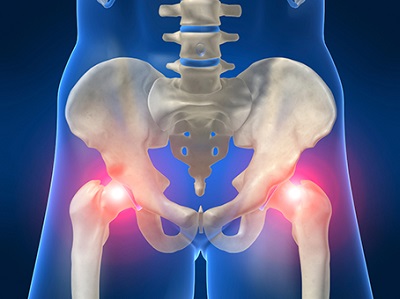

골반통증, 방치하면 큰 병 된다? 최근 들어 허리와 엉덩이 부위에서 느껴지는 ‘골반통증’ 때문에 고생하는 사람들이 늘고 있습니다. 특히 출산 후 여성이나 40대 이후 중년 여성에게 자주 나타나는 현상입니다.

이는 잘못된 자세로 장시간 앉아 있는 경우 근육 및 인대가 늘어나거나 손상돼 생길 수 있으면, 또한 평소 다리를 꼬고 앉거나 양반다리를 하고 앉는 습관도 골반통증의 원인이 될 수 있습니다.

하지만 대부분의 사람들은 이를 일시적인 근육통 정도로 생각하고 대수롭지 않게 여기곤 합니다. 그러나 문제는 골반통증을 그대로 방치할 경우 척추질환으로까지 이어질 수 있다는 점입니다.

따라서 초기에 적절한 치료를 받는 것이 무엇보다 중요하다는 점을 기억해야 합니다.